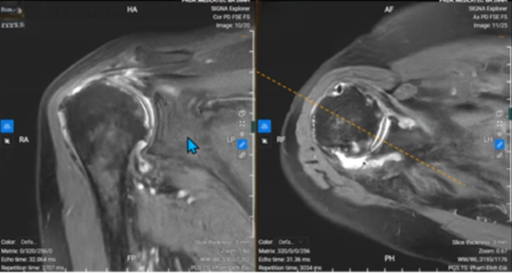

Để chẩn đoán bệnh viêm khớp dạng thấp, người ta thường dựa vào triệu chứng lâm sàng kết hợp với chẩn đoán hình ảnh và kết quả xét nghiệm của bệnh nhân.

Các xét nghiệm thăm dò bệnh gồm có: xét nghiệm yếu tố dạng thấp - RF, xét nghiệm anti - CCP, xét nghiệm ESR (tốc độ máu lắng), chụp X - quang,… Trong đó, xét nghiệm yếu tố dạng thấp và xét nghiệm anti - CCP là hai xét nghiệm quan trọng và chính xác nhất trong chẩn đoán bệnh.